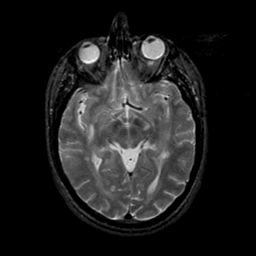

MR Study #21, November 3, 1991 -- Slice #22